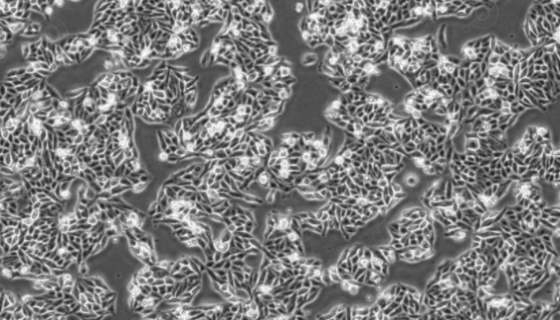

5637人膀胱癌細胞的應用與培養(yǎng)操作及研究動態(tài)!

5637人膀胱癌細胞可以用于SPTBN2基因在膀胱癌中的表達...